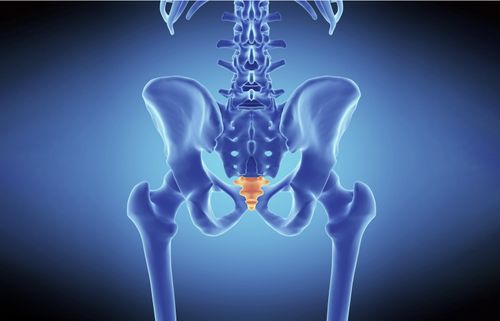

Sacroiliac Joint Pain

Sacroiliac Joint Injection